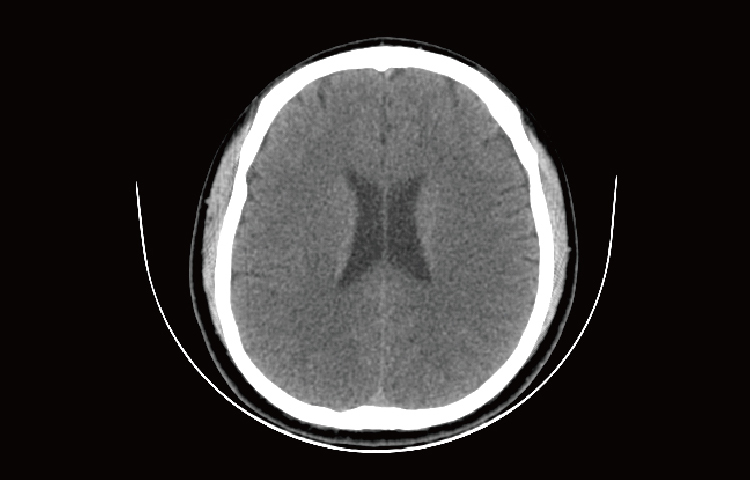

Скриншоты снимков